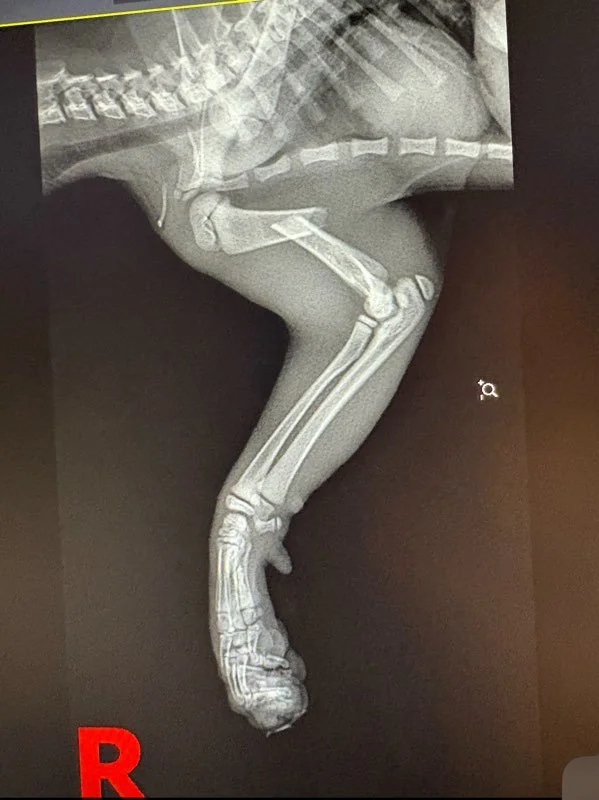

Moose was recently surrendered into LAWS’ care after a heartbreaking accident at home. This curious little kitten took a tumble from a three-level bunk bed, leaving him with a severely broken leg and in need of urgent medical attention.

Thanks to the incredible generosity of Orphan Kitten Club and Kitten Lady, Moose received a lifesaving medical grant that fully covered his surgery costs. Our wonderful partners at Gem City Veterinary placed a pin through his fractured leg, and Moose has been making an amazing recovery ever since!